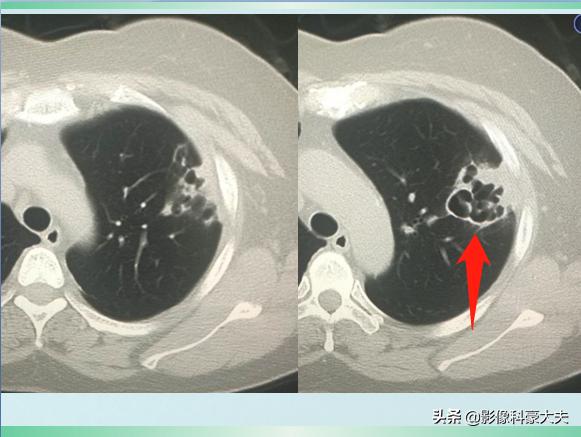

我们先不公布答案,继续看她治疗10天后的复查CT:

对比前两次片子,黑色空洞影变得更大了,周围的白色炎症斑片影吸收好转了。

这是一种什么细菌呢?为什么会短时间引起肺策划坏死空洞?经过实验室培养,医生们找到了真相——肺炎克雷伯杆菌。